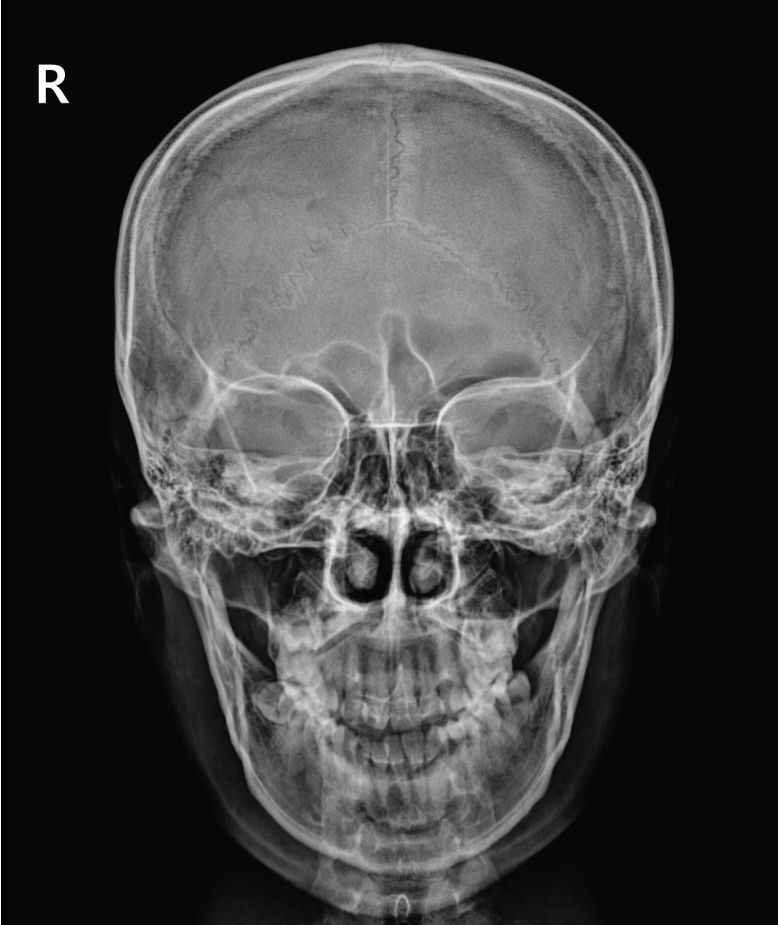

제 두개골 x레이인데요

2번째 사진에 접형골이 밑으로 내려와서 상악동이 좁아졌잖아요

이렇게 접형골 위치가 바뀌는게 가능한가요?

• 1번 째 사진